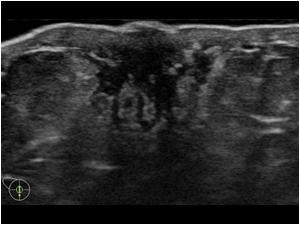

US of intracapsular rupture (step ladder sign)